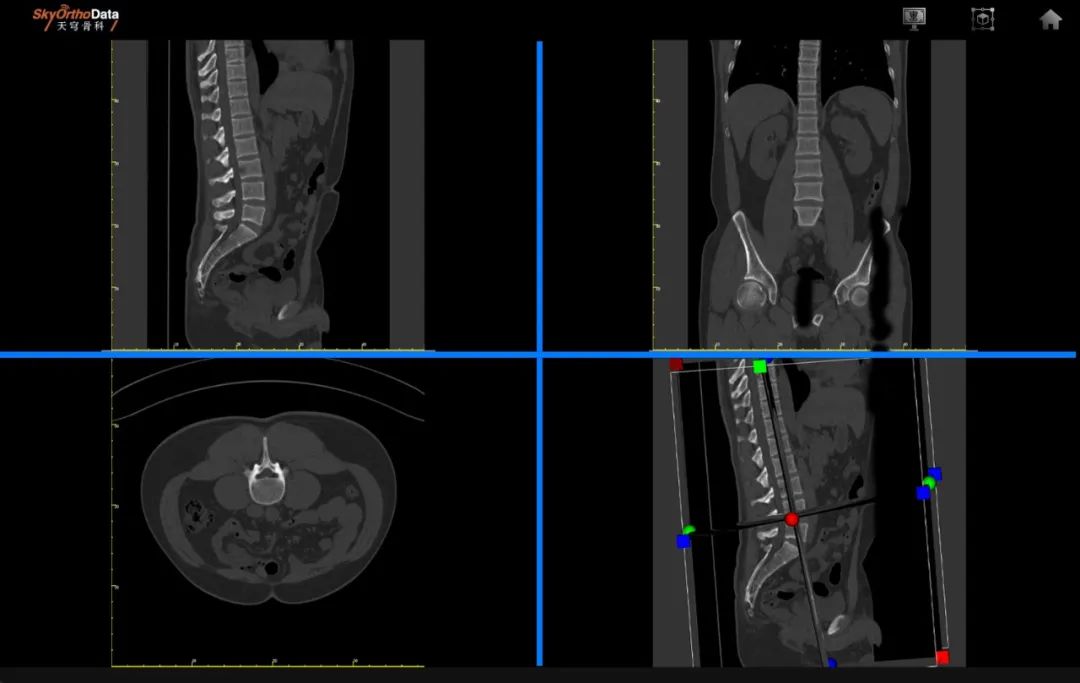

子課題(ti)“脊(ji)柱(zhu)(zhu)畸形(xing)智能(neng)(neng)影像(xiang)(xiang)評估及(ji)(ji)術(shu)前(qian)(qian)規劃(hua)新產品研(yan)發(fa)(fa)”利用(yong)EOS、MRI 等多模態(tai)的無輻射成像(xiang)(xiang)數據,開發(fa)(fa)基于深度(du)學習模型的脊(ji)柱(zhu)(zhu)畸形(xing)多維度(du)高清成像(xiang)(xiang)評估系統(tong),通過(guo)對臨床指標及(ji)(ji)解(jie)剖(pou)學參(can)數的自(zi)動化(hua)測量及(ji)(ji)圖像(xiang)(xiang)特征(zheng)提取,實現個性化(hua)術(shu)前(qian)(qian)規劃(hua),并為手術(shu)新器械的研(yan)發(fa)(fa)提供精(jing)準的結(jie)構化(hua)數據。德康(kang)醫療(liao)參(can)與脊(ji)柱(zhu)(zhu)畸形(xing)智能(neng)(neng)影像(xiang)(xiang)評估及(ji)(ji)術(shu)前(qian)(qian)規劃(hua)系統(tong)的開發(fa)(fa)及(ji)(ji)驗證(zheng)、專利申請、臨床應用(yong)研(yan)究(jiu)的培訓及(ji)(ji)輔(fu)助等工作(zuo),目前(qian)(qian)已完成算法開發(fa)(fa),提交(jiao)(jiao)專利1項,并同步進行國(guo)際PCT準備(bei)及(ji)(ji)提交(jiao)(jiao)。

在(zai)生產制造中心(xin),與(yu)會專(zhuan)家(jia)們觀摩了包(bao)括(kuo)高(gao)精(jing)度加工設(she)備和(he)自動化(hua)生產線(xian)在(zai)內的(de)智(zhi)能制造模式。在(zai)研發中心(xin),與(yu)會嘉賓對德(de)康醫(yi)療鯤鵬生物力學實(shi)驗室所開展的(de)各(ge)種骨(gu)科(ke)植入物及材(cai)料的(de)靜(jing)態與(yu)疲勞性能研究檢(jian)測、生物力學與(yu)有限元仿真(zhen)分析等項目進行了深入溝通(tong)交流;智(zhi)能骨(gu)科(ke)超算中心(xin)現場介紹天穹骨(gu)科(ke)數(shu)據庫(ku),直觀展示數(shu)據庫(ku)基于(yu)AI的(de)在(zai)線(xian)3D閱片(pian)功能。專(zhuan)家(jia)們也結合臨床實(shi)踐中積(ji)累的(de)寶(bao)貴經(jing)驗,就如何更好地將創新技術應用于(yu)實(shi)踐、實(shi)現醫(yi)工融合提出了寶(bao)貴意見和(he)建議。